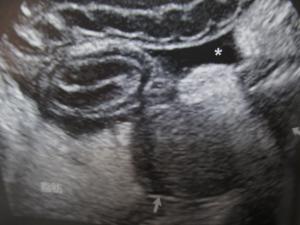

先日、大阪府立大学で研究会がありました。夜の9時半から診療を終えた開業の獣医師と大学の先生方も集まって総勢50人ぐらいで順番で自分の症例を発表していきます。当院からは田端先生が“犬の急性壊死性膵炎の一例”を発表しました。突然嘔吐を繰り返すという厄介なプードルちゃんの話でした。急性膵炎は普通によく見られる症例なので、数多くのご指摘ご意見を頂戴しました。今回はオーナー様が非常に熱心な方で腹部のエコー像が綺麗に撮れて経過の診断に役立ちました。病院に持ち帰って是非次の症例に生かしていきたいと考えています。